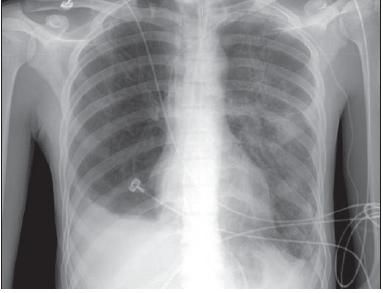

Four weeks later, the patient began to show signs of slow improvement. The tracheotomy tube was removed, and a tracheostomy button was safely put in place. The patient continued to improve, and his chest radiograph showed resolution (Figure 4). He was discharged for rehabilitation after almost 8 weeks of hospitalization. At followup visits, he was noted to have achieved a full recovery without any functional limitations.

Figure 4 –

This anteroposterior chest radiograph

confirms complete resolution before the patient's discharge.